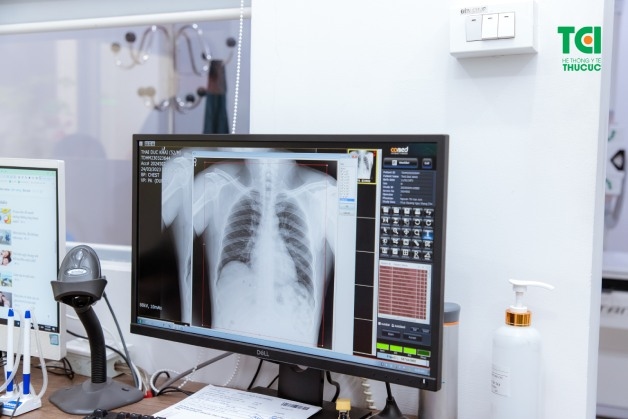

2.1. Chụp X-quang phổi

Gần như các khối u phổi xuất hiện trên tia X dưới dạng một khối màu trắng. Tuy nhiên, phương pháp chụp X-quang không thể đưa ra các chẩn đoán chính xác bởi không thể phân biệt được giữa ung thư và các tình trạng khác.

Chụp X-quang phổi được thực hiện nhanh chóng và không gây khó chịu cho người bệnh